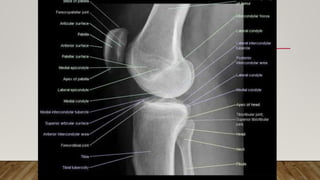

This document discusses radiology and the use of x-rays. It begins with an introduction to radiology and x-rays, noting their importance as the "father of medical investigations." It then discusses anatomy as seen on radiographs and whether x-rays are enough. The document goes on to compare gross views to radiological views, noting what each can and cannot show. It highlights important figures in the development of radiology, from x-rays to CT, MRI, and ultrasound. Specific anatomical structures visible on upper and lower limb x-rays are listed. The document concludes by discussing how pathologies appear on x-rays and the importance of clinical history and knowledge when interpreting radiological images.